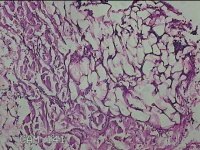

右后颈部包块

性别

女

年龄

31岁

临床诊断

头颈皮脂腺囊肿

一般病史

发现后颈部包块1年余。

标本名称

大体所见

灰白粉红色包块2.3x1.5x0.8cm一个,表面光滑,带少许脂肪,部分已切开,切面灰白粉红色,质中。

图1

制片质量、图片信息影响判读。